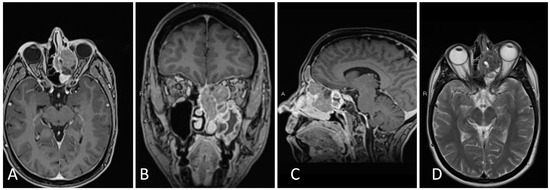

3.1.2. Illustrative Case

3.1.4. Illustrative Case